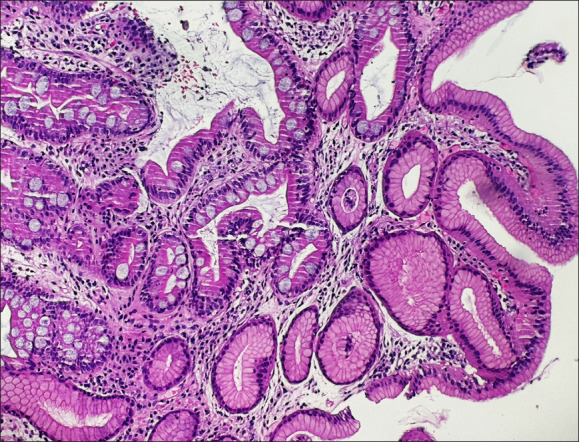

Abstract Image